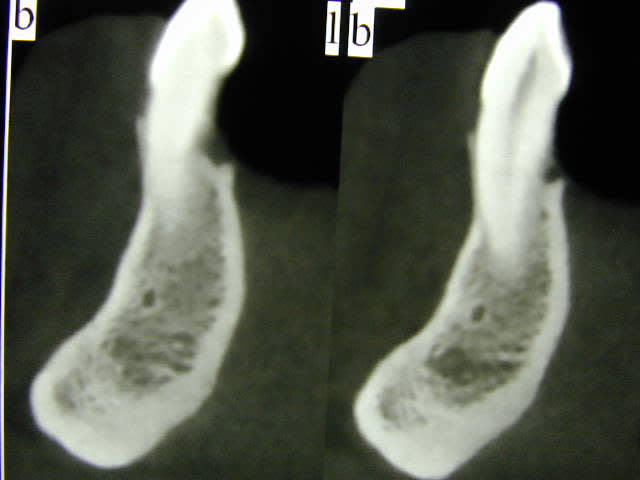

2)Sur le scanner j'ai l'image du nerf dentaire et d'un nerf en dessous, de quoi s'agit-il ?

> 2)Sur le scanner j'ai l'image du nerf dentaire et d'un nerf en dessous, de quoi s'agit-il ?

l'artère alvéolaire non ? en zone de spix elle est dessus puis dans son trajet mandibulaire en dessous du NAI